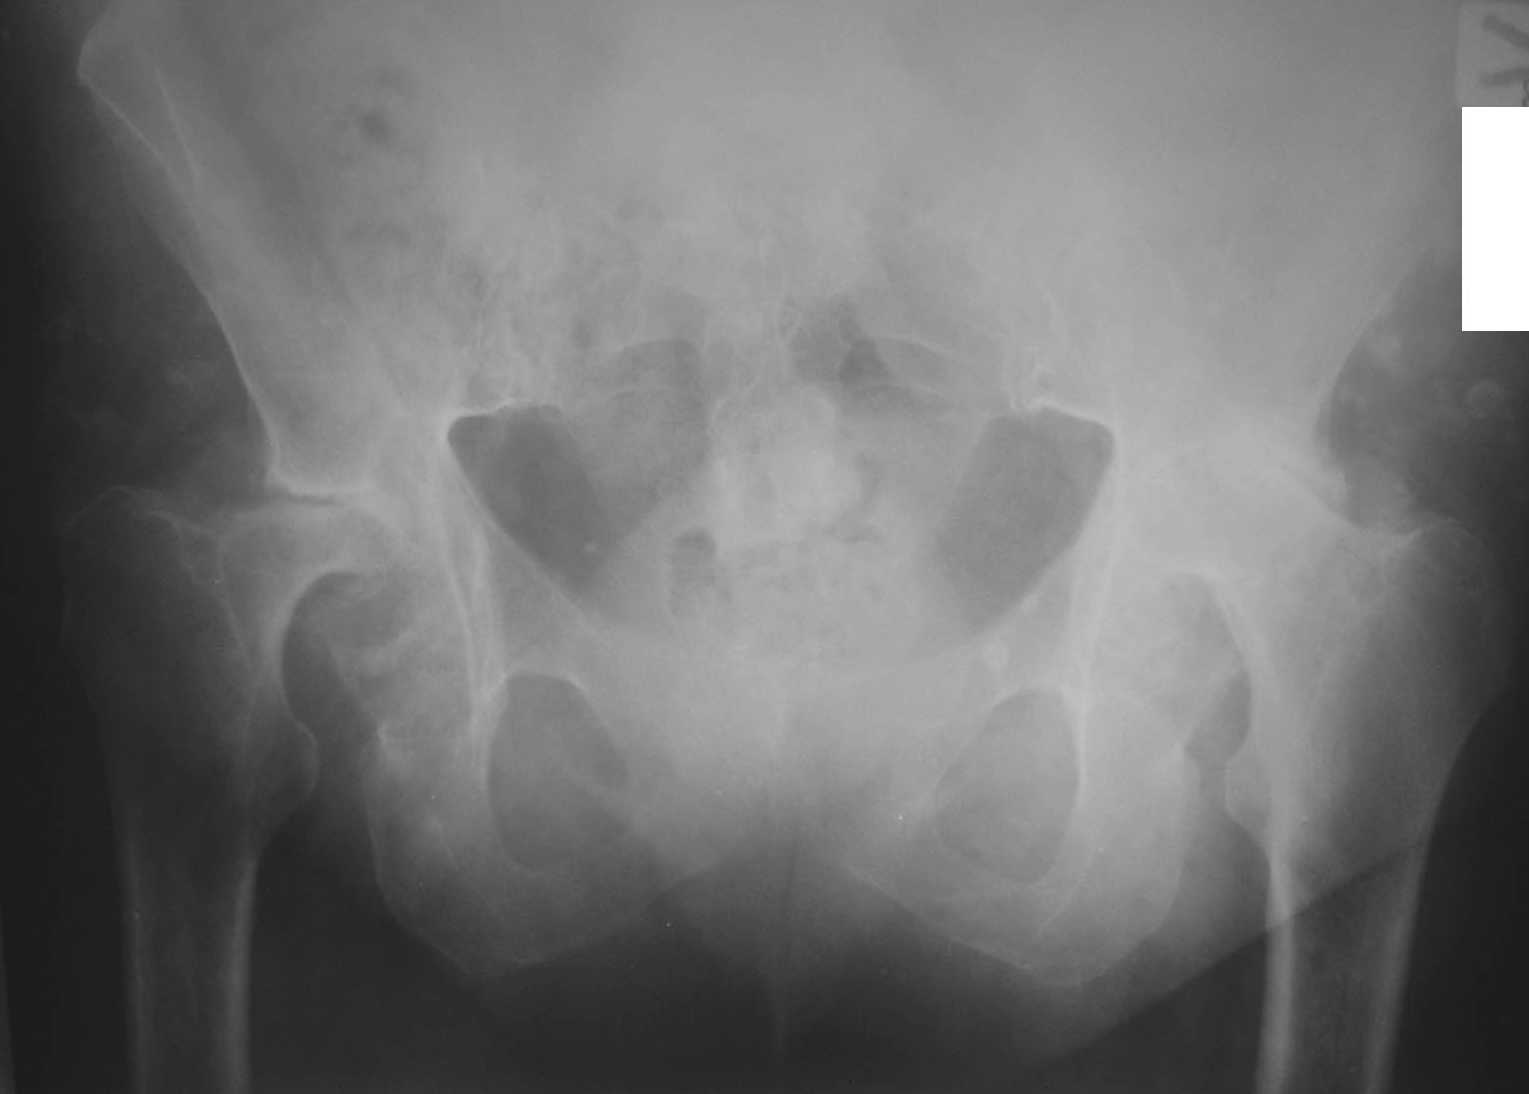

Пациентка С., женщина, 50 лет. Ревматоидный полиартрит. Двусторонний ревматоидный артрит тазобедренных суставов.инвалид 1-й гркппы. Принимает гормоны.

Вопрос: с учетом возраста и состояния костной ткани - цементную или бесцементную технологию эндопротезирования выбрать?

Заранее благодарю! Female, 50 y.o. DS: Rehumatoid polyarthritis, both-sides rehumatoid coxaarthritis. She has hormone therapy. We are going to perform arthroplasty.

Which kind do you prefer in this situation (cemented or cemented-less)?